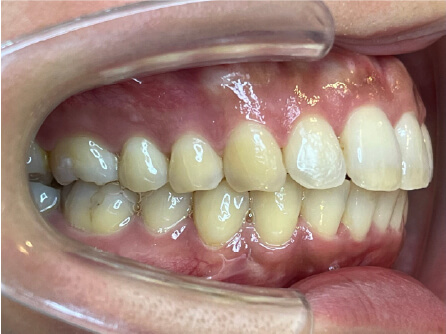

叢生の症例

41歳

女性

横から見た時のガタガタが気になる

インビザライン、正中は上11に合わせていく、抜歯・拡大装置・IPR・アタッチメントOK

アライナー矯正

クリアライナー使用

痛み・歯根吸収・歯肉退縮・虫歯・後戻り

880,000円、7ヶ月